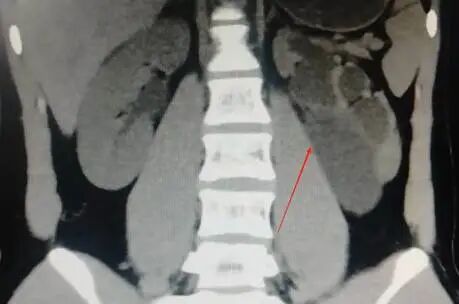

患者术前影像学检查

结合影像检查、及其年龄(18岁)和无结石、手术等病史的特点,医生判断小元是先天性肾盂输尿管连接部狭窄。此类狭窄在儿童和青少年中较为常见,多因先天因素引发,如肾盂输尿管连接部的平滑肌发育异常、先天性瓣膜或息肉等;成人则可能因手术损伤、慢性炎症等后天因素患病,而小元的情况属于典型的先天性病变。

为明确诊断并控制感染,泌尿外科熊海群医生与郭天旺医生为小元进行了输尿管镜检查,结果证实其左侧输尿管上段近肾盂处存在明显狭窄,输尿管镜无法通过,但导丝可插入,于是医生为小元置入了双J管(输尿管支架)以引流并控制感染,也为后续手术做好准备。